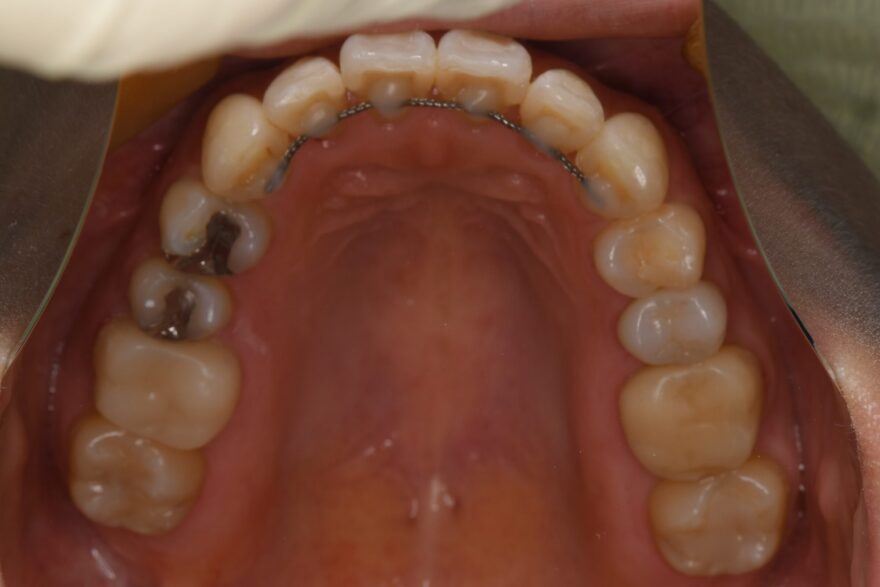

上下の変化はこちら!

凄くきれいに整ったと思いませんか??

これから銀歯や昔の詰め物を取り換えていくので、さらに美しい口腔内になると思います!!